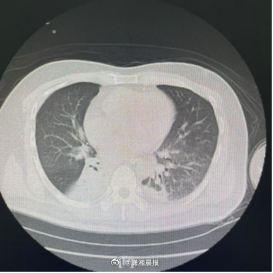

术后复查胸部CT显示:原本不张的右下肺已基本复张。医生再次尝试堵管,张大爷呼吸平稳,没有丝毫憋闷感。